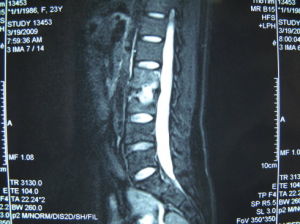

MRI具有早期診斷的價值,在炎性浸潤階段即可顯示異常信號,但主要用於觀察脊髓有無受壓和變性。